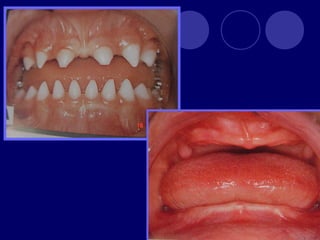

AMELOGENESIS IMPERFECTA  Hipoplásico: Zonas ausentes de esmalte  Afecta más a caras vestibulares  Esmalte: blanco amarillento y marrón claro, consistencia dura, fosas y surcos oscuras, delgado  Hipocalcificado:  Cualitativo  Esmalte frágil, fácil de desprender  Rx: falta de contacto entre dentina, esmalte  Hipomaduro:  Disminución en el contenido mineral  Esmalte blando y rugoso, veteado de blanco a marrón (esmalte en copos de nieve)  Más frecuente en caras vestibulares y dientes superiores

DISPLASIA AMBIENTAL DEL ESMALTE HIPOPLASIA POR INGESTA DE FLÚOR: fluorosis, manchas opacas, esmalte sin brillo(leve=lechoso, graves=amarillo/café) .